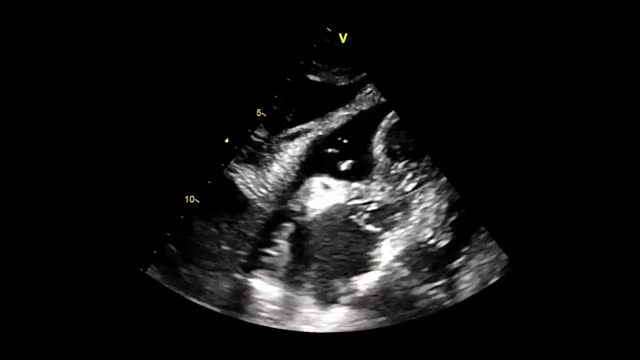

To assess the CVC tip position, one operator injects agitated saline or normal saline through the distal port of the CVC, while a second operator performs simultaneously a subcostal 4 chamber view or an apical 4 chamber view. The immediate (within 2 s) appearance of turbulent flow in the right atrium is known as the rapid atrial swirl sign (RASS) and predicts with excellent sensitivity and specificity for a correct catheter tip positioning45 (Video 1).

Ultrasound-guided pericardiocentesis. A) Subcostal 4 chamber view. B) Parasternal long-axis view. C) Apical view. As noted, the optimal window to insert the needle is the apical, given the shorter distance to reach the pericardial space (continuous green line) and higher pericardial fluid thickness (continuous yellow line). RA, right atrium; RV, right ventricle; LA, left atrium; LV, left ventricle; RVOT, right ventricular outflow tract. Asterisks indicate pericardial effusion. Adapted from Blanco P, Figueroa L, Menéndez MF, Berrueta B. Pericardiocentesis: ultrasound guidance is essential. Ultrasound J. 2022;14(1):9. https://theultrasoundjournal.springeropen.com/articles/10.1186/s13089-022-00259-5. (CC-BY-4.0). D) Recognition of the left internal thoracic vessels along the left parasternal line (dotted white line) with a linear probe on two-dimensional and color Doppler imaging; s-sct, skin-subcutaneous tissue; m, intercostal muscle; r, rib; arrowhead, pleura; asterisks, internal thoracic vessels. E) Recognition of the intercostal vessels with a linear probe on color Doppler imaging. Real-time in-plane ultrasound-guided pericardiocentesis via intercostal approach (apical view) using a linear probe. The needle (arrows) is entirely observed in the pericardial space (asterisks); LV: left ventricle. G) Hemorrhagic fluid is freely evacuated from the pericardial space after catheter placement.